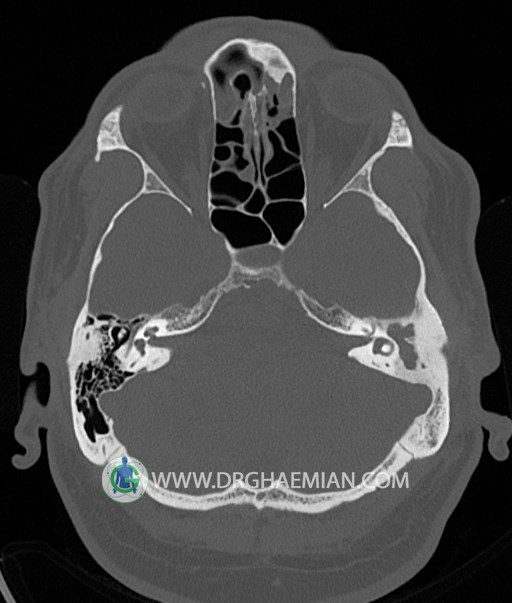

سی تی اسکن گوش داخلی به رادیولوژیست اجازه می دهد تا سطوح مختلف، یا اسلایس هایی از استخوان های که از جمجه به گوش می روند را از طریق امواج ایکس چرخشی مشاهده کند. در این کیس اودیت مدیا، ماستوئیدیت مزمن، اوتیت خارجی، انحراف سپتوم بینی، کونکا بولوزا و افزایش ضخامت سینوس ها مشاهده می شود.

در HRCT از استخوان تمپورال با مقاطع آگزيال ، ساژيتال و کرونال ظريف ( 0.6 mm ) :

– اپاسيتي گوش مياني چپ ناشي از وجود دانسيته نسج نرمي دراطراف استخوانچه ها همراه با اروژن اسکوتوم و

استخوانچه ها بدون جابجايي در رديف استخوانچه ها مشهود است که مطرح کننده اوتيت مديا همراه با نشانه

هاي مشکوک به کولستئاتوم مي باشد .

– اپاسيتي و اسکلروزيس ماستوئيد چپ نشانه ماستوئيديت مزمن

– اپاسيتي کانال گوش خارجي ناشي از دانسيتي نسج نرمي مطرح کننده external otitis